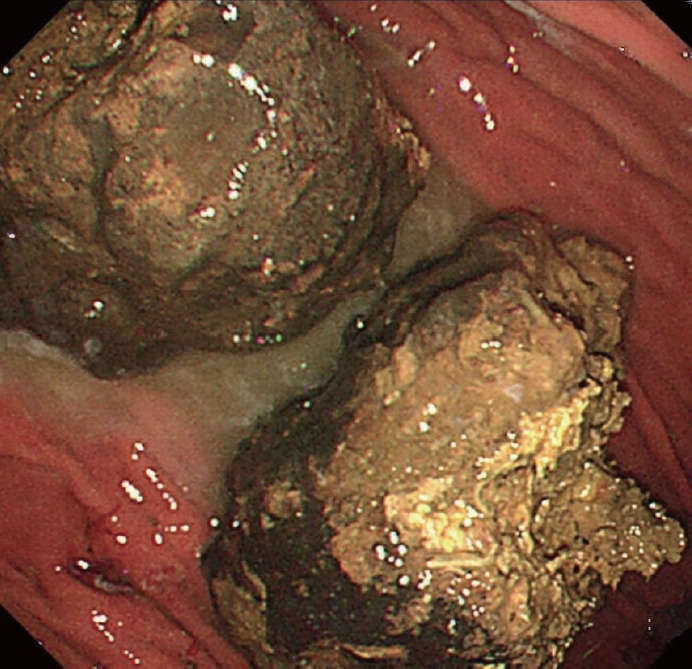

牛黄是一种难以消化的物质,可引起胃肠道并发症,如阻塞和穿孔。我们报告的情况下,60岁的男子与2型糖尿病和十二指肠溃疡手术史。患者出现大量胃植粪,引起持续性消化不良和胃脘痛。胃镜检查证实胃角处有10厘米的植物性牛黄和1.5厘米的活动性溃疡。为了软化牛黄,病人服用了可口可乐和纤维素酶。这种治疗方法显著降低了牛黄的硬度,使其能够成功地使用常规设备进行内窥镜碎裂。在三次内窥镜检查中,牛黄被粉碎成小于1厘米的碎片并被取出;此后,胃溃疡完全愈合。本病例说明了将可口可乐和纤维素酶的作用与内窥镜方法结合治疗大牛黄的有效性,为社区卫生保健机构提供了一种手术方法的替代方法。

Bezoars are indigestible masses that can cause gastrointestinal complications such as obstructions and perforations. We report the case of a 60-year-old man with a history of type 2 diabetes mellitus and duodenal ulcer surgery. The patient developed a large gastric phytobezoar that caused persistent dyspepsia and epigastric pain. Upper endoscopy confirmed a 10-cm phytobezoar and a 1.5-cm active ulcer at the gastric angle. To soften the bezoar, Coca-Cola and cellulase were administered to the patient. This treatment significantly reduced the bezoar's hardness, permitting its successful endoscopic fragmentation using conventional devices. Over three endoscopic sessions, the bezoar was fragmented into pieces smaller than 1 cm and removed; thereafter, the gastric ulcer healed completely. This case illustrates the effectiveness of combining the actions of Coca-Cola and cellulase with endoscopic methods to treat large bezoars, providing an alternative to surgical approaches in community healthcare settings.